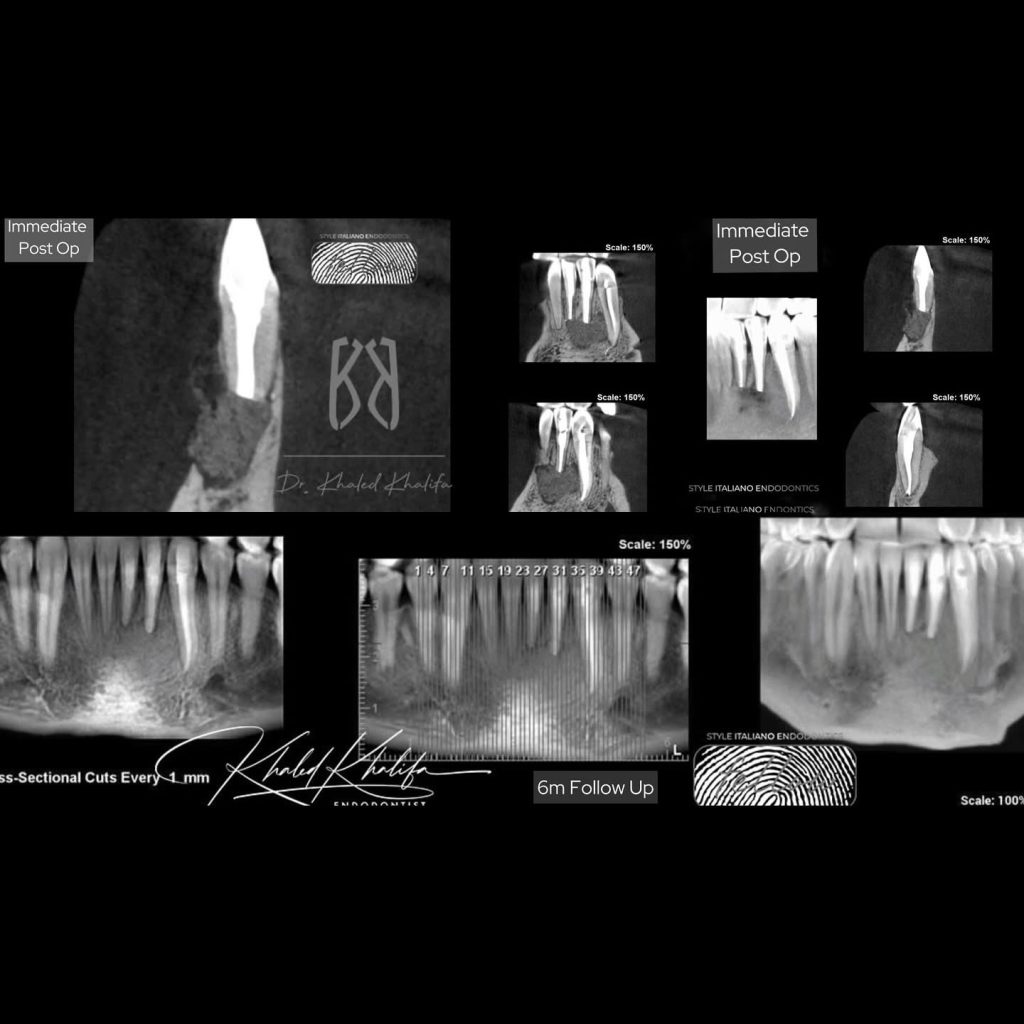

𝖳𝗁𝗂𝗌 𝖼𝖺𝗌𝖾 𝗂𝗌 𝖺 𝗍𝗒𝗉𝗂𝖼𝖺𝗅 𝖼𝖺𝗌𝖾 𝗈𝖿 𝙄𝙣𝙛𝙚𝙘𝙩𝙚𝙙 𝙧𝙖𝙙𝙞𝙘𝙪𝙡𝙖𝙧 𝙘𝙮𝙨𝙩, 𝗐𝗁𝖾𝗋𝖾 𝗍𝗁𝖾 𝗉𝖺𝗍𝗂𝖾𝗇𝗍 𝗌𝗎𝖿𝖿𝖾𝗋𝖾𝖽 𝖿𝗋𝗈𝗆 𝗆𝗎𝗅𝗍𝗂𝗉𝗅𝖾 𝖺𝖻𝗌𝖼𝖾𝗌𝗌 𝖺𝗇𝖽 𝗍𝗁𝖾𝗒 𝖺𝗋𝖾 𝖺𝗅𝗅 𝗋𝖾𝖼𝗎𝗋𝗋𝖾𝗇𝗍. 𝖤𝗏𝖾𝗇 𝗍𝗁𝗈 𝗌𝗁𝖾 𝗁𝖺𝖽 𝗉𝖾𝗋𝖿𝖾𝖼𝗍 𝗋𝗈𝗈𝗍 𝖼𝖺𝗇𝖺𝗅 𝗍𝗋𝖾𝖺𝗍𝗆𝖾𝗇𝗍 𝖳𝖶𝖨𝖢𝖤 𝖻𝗎𝗍 𝗎𝗇𝖿𝗈𝗋𝗍𝗎𝗇𝖺𝗍𝖾𝗅𝗒 𝗌𝗈𝗆𝖾𝗍𝗂𝗆𝖾𝗌 𝗍𝗁𝖾 𝗌𝗈𝗅𝗎𝗍𝗂𝗈𝗇 𝗂𝗌 𝙢𝙞𝙘𝙧𝙤 𝙖𝙥𝙞𝙘𝙖𝙡 𝙨𝙪𝙧𝙜𝙚𝙧𝙮.

5. Root resection & Retrograde prep using 𝘂𝗹𝘁𝗿𝗮𝘀𝗼𝗻𝗶𝗰𝘀 specifically designed for 𝗿𝗲𝘁𝗿𝗼 𝗰𝗮𝘃𝗶𝘁𝘆 𝗽𝗿𝗲𝗽, 𝐦𝐢𝐜𝐫𝐨 𝐦𝐢𝐫𝐫𝐨𝐫𝐬 and the 𝐫𝐞𝐟𝐥𝐞𝐜𝐭𝐢𝐧𝐠 𝐬𝐢𝐝𝐞 𝐨𝐟 𝐌𝐢𝐧𝐧𝐞𝐬𝐨𝐭𝐚 helps in 𝐢𝐧𝐝𝐢𝐫𝐞𝐜𝐭 𝐯𝐢𝐬𝐢𝐨𝐧.

7. Trying the retro plugger to see if it fits then packing 𝗯𝗶𝗼𝗰𝗲𝗿𝗮𝗺𝗶𝗰 𝗺𝗮𝘁𝗲𝗿𝗶𝗮𝗹 in proper thickness to seal it.